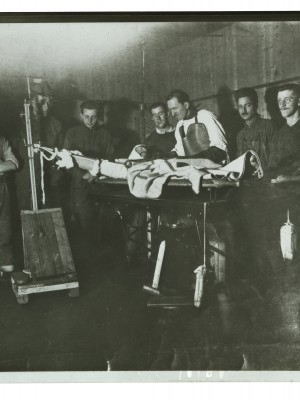

Dr. Edwin Ernst, an only child born to St. Louis residents Charles and Catherine Ernst, was a notable Roentgenologist, a physician who specializes in radiological work. Dr. Ernst studied at Washington University in St. Louis and later at Moravian College in Bethlehem, Pennsylvania earning his advanced degrees. For two years he served as a resident physician at the St. Louis Mullanphy Hospital before leaving to pursue a private practice. When the United States formally entered the war in 1917, Ernst left St. Louis to become chief radiologist at Base Hospital 21. He was discharged honorably in 1919 with the citation of Major. His collection consist of x-ray images taken at Base Hospital 21 as well as drawings of radiological equipment and photographs.